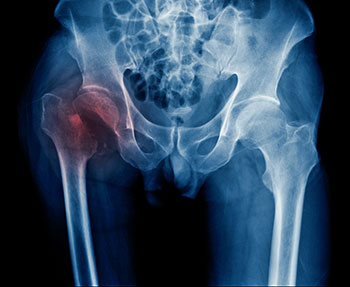

This clinical practice guideline is intended for use with adults aged 65 years and older who have been diagnosed with hip fracture. (The lower limit for the patient population was set at 55 years of age but was also required to have an average age of 65 years).